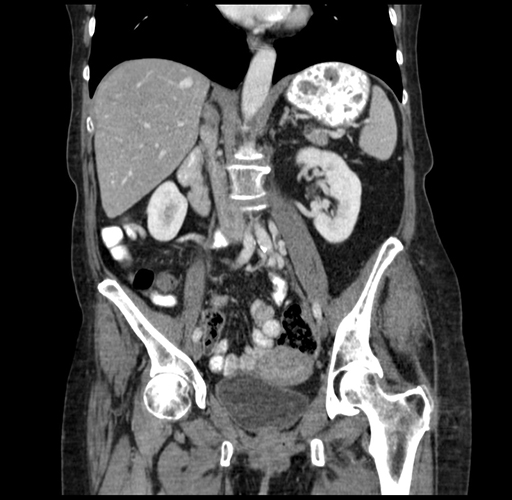

Coronal Venous